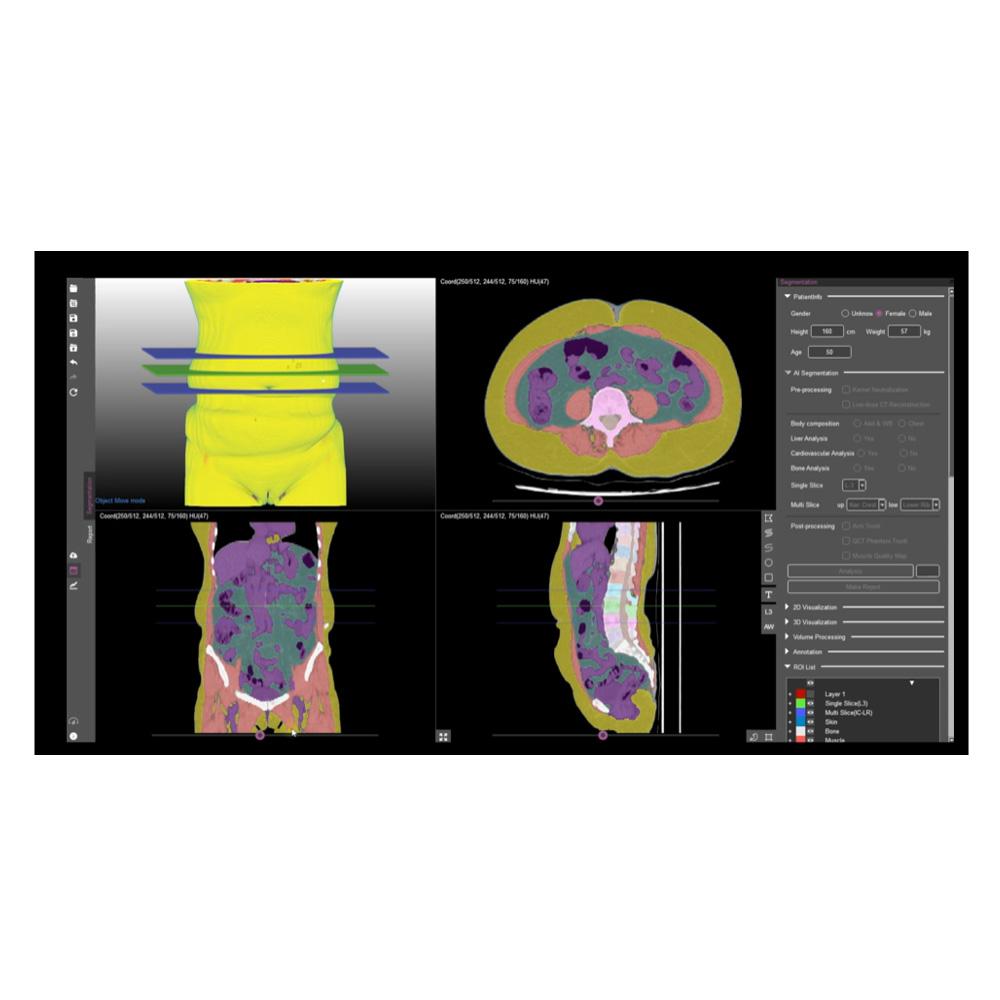

Automatic Analysis of Body Composition Based on CT

Over 7 x-layers in total

(skin, bones, muscles, visceral fat, subcutaneous fat, etc.)

Whole body segmentation

-Skin, bones, muscles, visceral fat, subcutaneous fat, organs, cerebrospinal fluid, etc

-Skin, bones, muscles, visceral fat, subcutaneous fat, organs, cerebrospinal fluid, etc

Automatic segmentation of body composition structures

Automatic analysis of AI-based body composition and provision of quantitative information